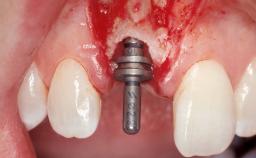

Placement Protocol Immediate implant placement

Socket Morphology Single-root socket

Socket Integrity Sufficient, with intact bone walls

Bone Volume Sufficient, with intact walls

Complexity Moderate

Risk of Complications High